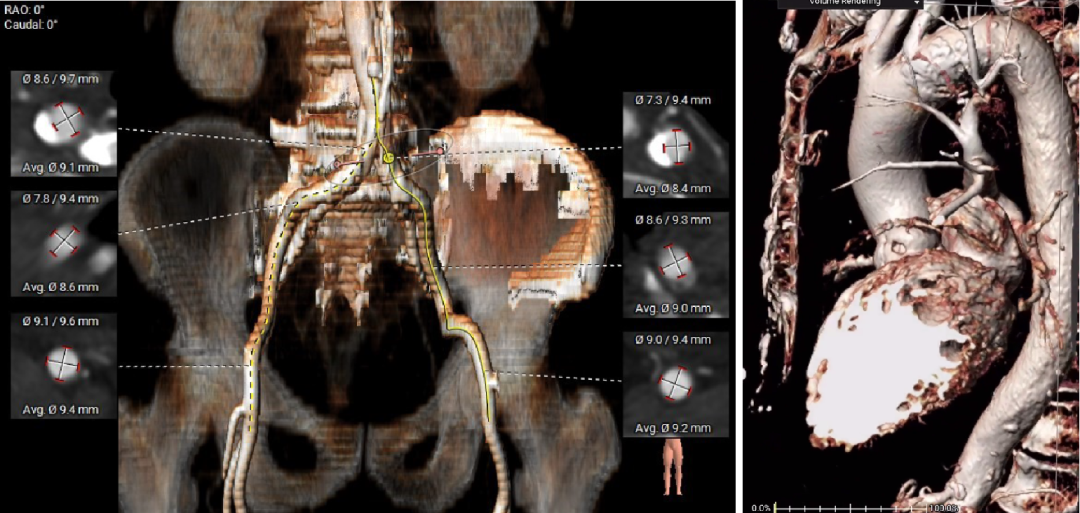

范嘉祺教授就CT在TAVR术前评估及手术策略制定展开了深入讲解。TAVR术前CT评估主要包括:1、入路血管的评估选择入路方式;2、主动脉根部解剖的评估制定球囊、瓣膜选择策略;3、心室大小、冠状动脉阻挡风险等。4、相比西方国家,我国二叶瓣比较高,且产生严重钙化的比例也较高,以往根据瓣环选择瓣膜的策略可能带来风险。故针对国内患者的情况,需要术前更加精细的瓣上结构分析,并结合术中球扩,优化瓣膜选择策略,提高手术的安全性和有效性。

精彩的理论授课外,王建安教授团队通过一例复杂的TAVR手术演示,全面展示了Hangzhou Solution在评估瓣上结构,指导二叶瓣TAVR手术策略的应用,以及可回收系统在复杂病变中给临床带来的获益。

外周入路